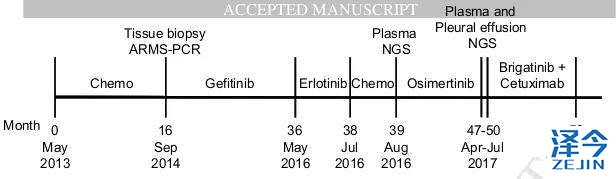

患者,女,62岁,无吸烟史,2013年5月因胸腔积液入院检查并治疗,被确诊为Ⅳ期肺腺癌。

化疗,一代TKI治疗后,病情依旧进展

患者先进行化疗,基因检测显示为EGFR 19号外显子缺失,开始使用一代TKI药物治疗。一代TKI耐药后,发现患者出现T790M突变。

奥西替尼AZD9291治疗,病情稳定一段时间后,继续进展

因此,患者开始接受每日80mg的奥西替尼AZD9291治疗,患者在一个月内达到了病情稳定(SD),CA125水平迅速下降,经过8个月的无进展生存期,患者肺左下叶出现新的病灶,胸腔积液增多,病情发展。

布加替尼联合西妥昔单抗治疗,病情长期稳定控制

患者再次基因检测发现T790M-C797S顺式突变,因此在2017年7月开始联合使用布加替尼(90mg/日)和西妥昔单抗(600mg/月),治疗一个月时,患者的疲劳和呼吸困难明显改善,CA125水平明显下降,直到2018年4月病情一直稳定(PFS为9个月),除了轻度疲劳外无其他的不良反应。虽然在2018年4月患者出现脑转移灶,但在2018年9月,患者的胸部病灶依旧得到很好的控制。